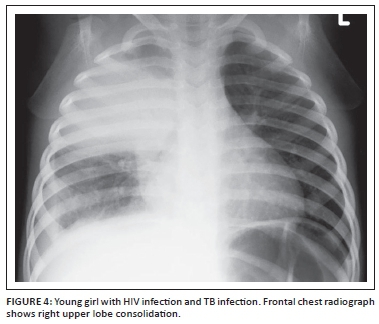

In areas with a high incidence of tuberculosis such as Africa, Mycobacterium tuberculosis (TB) is an important cause of acute and chronic respiratory infection in HIV- infected children. They have an increased risk of developing complicated or disseminated disease.5 Standard TB therapy is less efficacious with lower cure rates and higher mortality.9 Co-infection with TB and HIV results in more rapid deterioration in immune function, viral replication and eventually HIV progression.9 Other fungal infection such as chronic oropharyngeal, laryngeal or oesophageal Candida albicans infection is also common and may result in dysmotility, gastro-oesophageal reflux disease and/ or aspiration and present with respiratory symptoms.10

TB is commonly encountered in children infected with HIV. On chest radiographs, TB infection typically presents with lung parenchymal disease characterised by either 'tree-in-bud' pattern small nodular opacities or consolidation (Figure 4). Mediastinal and hilar lymphadenopathy is also typically present. In comparison to immunocompetent children with TB infection, extensive lung disease with cavitation occurs more frequently in HIV-infected children (Figure 5).5 Although CT is associated with potentially harmful radiation exposure, CT can better detect and characterise thoracic infections from TB. Enlarged mediastinal and hilar lymph nodes demonstrating central low attenuation and peripheral contrast enhancement should suggest TB infection in children with HIV infection especially when lung parenchymal disease is concomitantly present.16,17 With concerns about radiation exposure from CT imaging, alternative imaging modalities which are not associated with radiation exposure such as ultrasound and MRI are currently gaining favor particularly in the pediatric population.